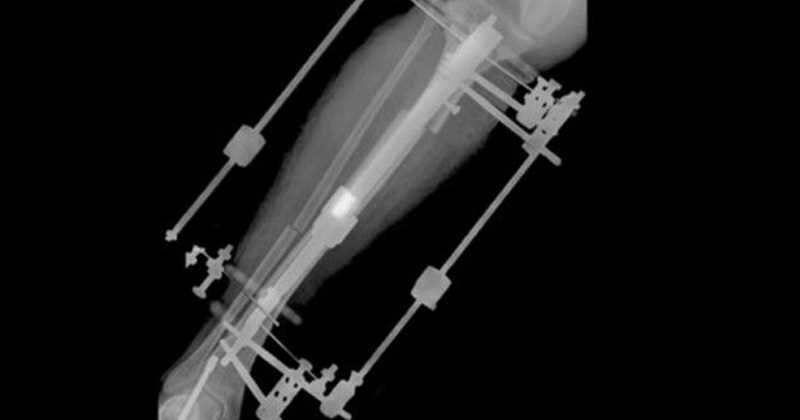

Tras fracturarle el hueso de la tibia en dos sitios, le colocaron dos aparatos fijadores externos unidos al hueso mediante dos tornillos largos.

El dispositivo fijador externo permite alargar la tibia un milímetro al día.